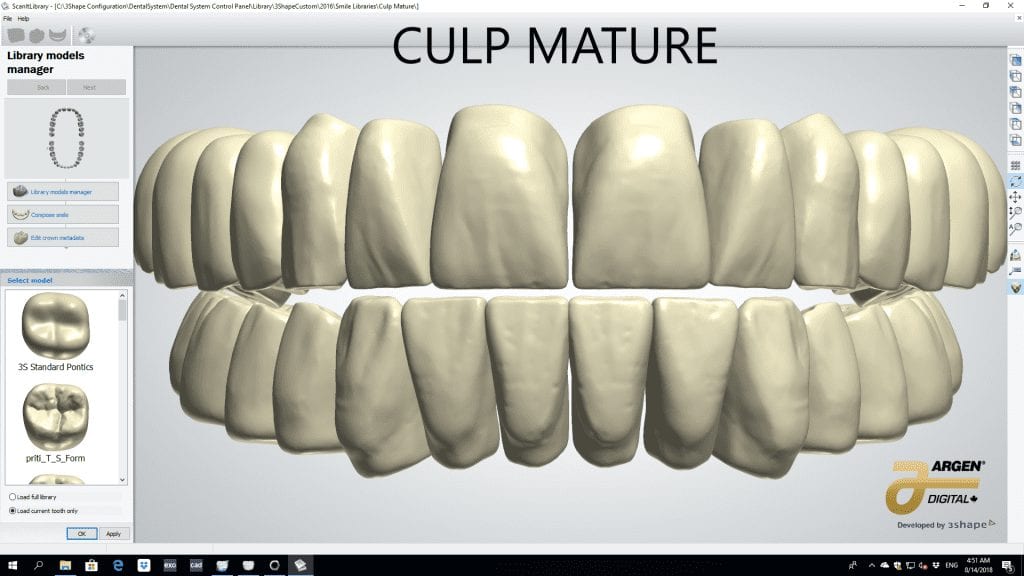

The digital models were then imported into a third party software where a library of tooth morphologies are available for the clinician to choose from.

Once the appropriate library is chosen, the digital wax ups are performed. In the subsequent photos you can see the transparent overlay of the wax-ups to the original position of the existing dentition